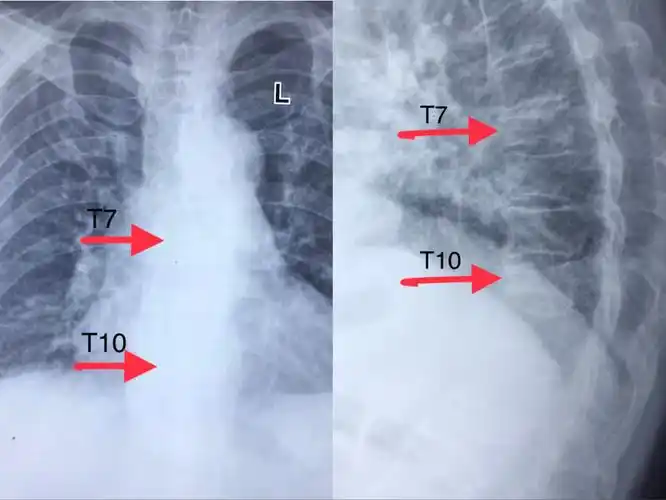

甘肃省中医院帮扶队在陇西县中医院骨二科成功开展全县首例双胸椎